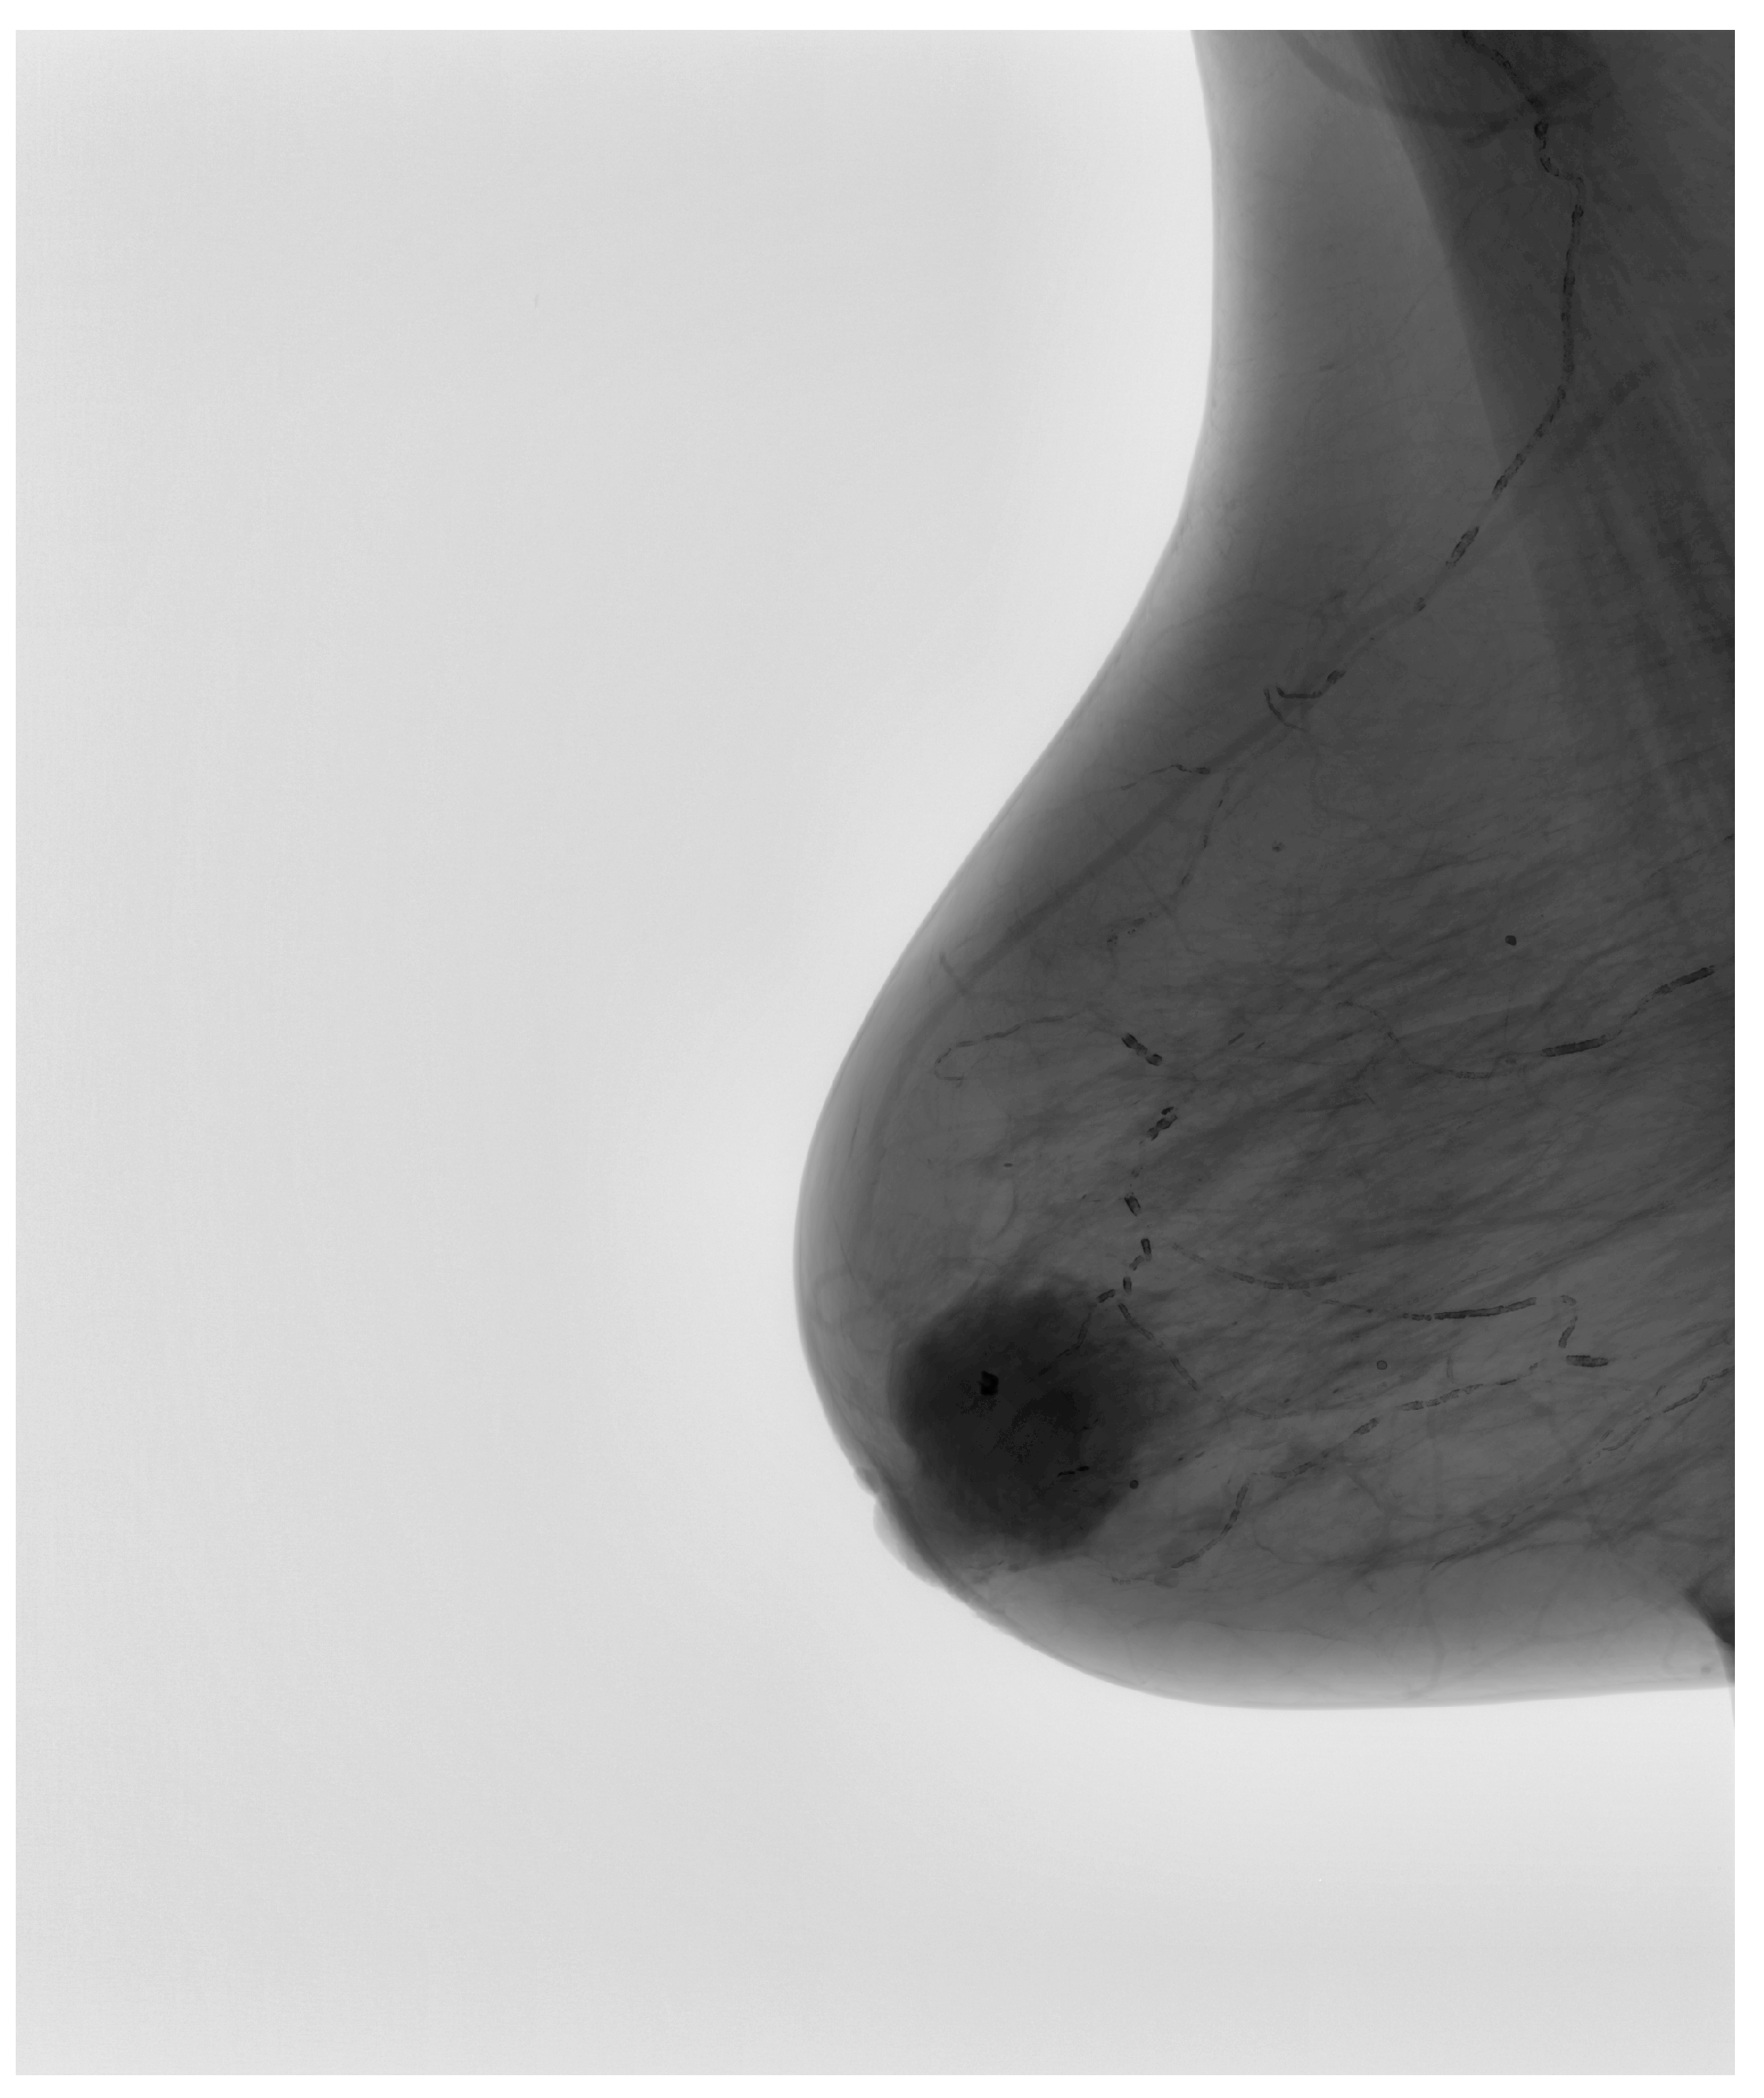

The final stage of preprocessing involved the application of image-sharpening techniques aimed at enhancing edge definition. Given that the appearance of suspicious lesions, including architectural distortions and microcalcifications, relies on their edge characteristics, sharpening the image facilitated better delineation of these features. Figure 4 demonstrates the final processed mammographic image optimized for subsequent AI training. The combination of CLAHE, noise reduction, and sharpening ensured that each image provided maximum diagnostic information while maintaining a standardized format, reducing heterogeneity that could otherwise compromise the learning process of the AI model.

Figure 4.

Final processed image, optimized for deep learning-based classification.